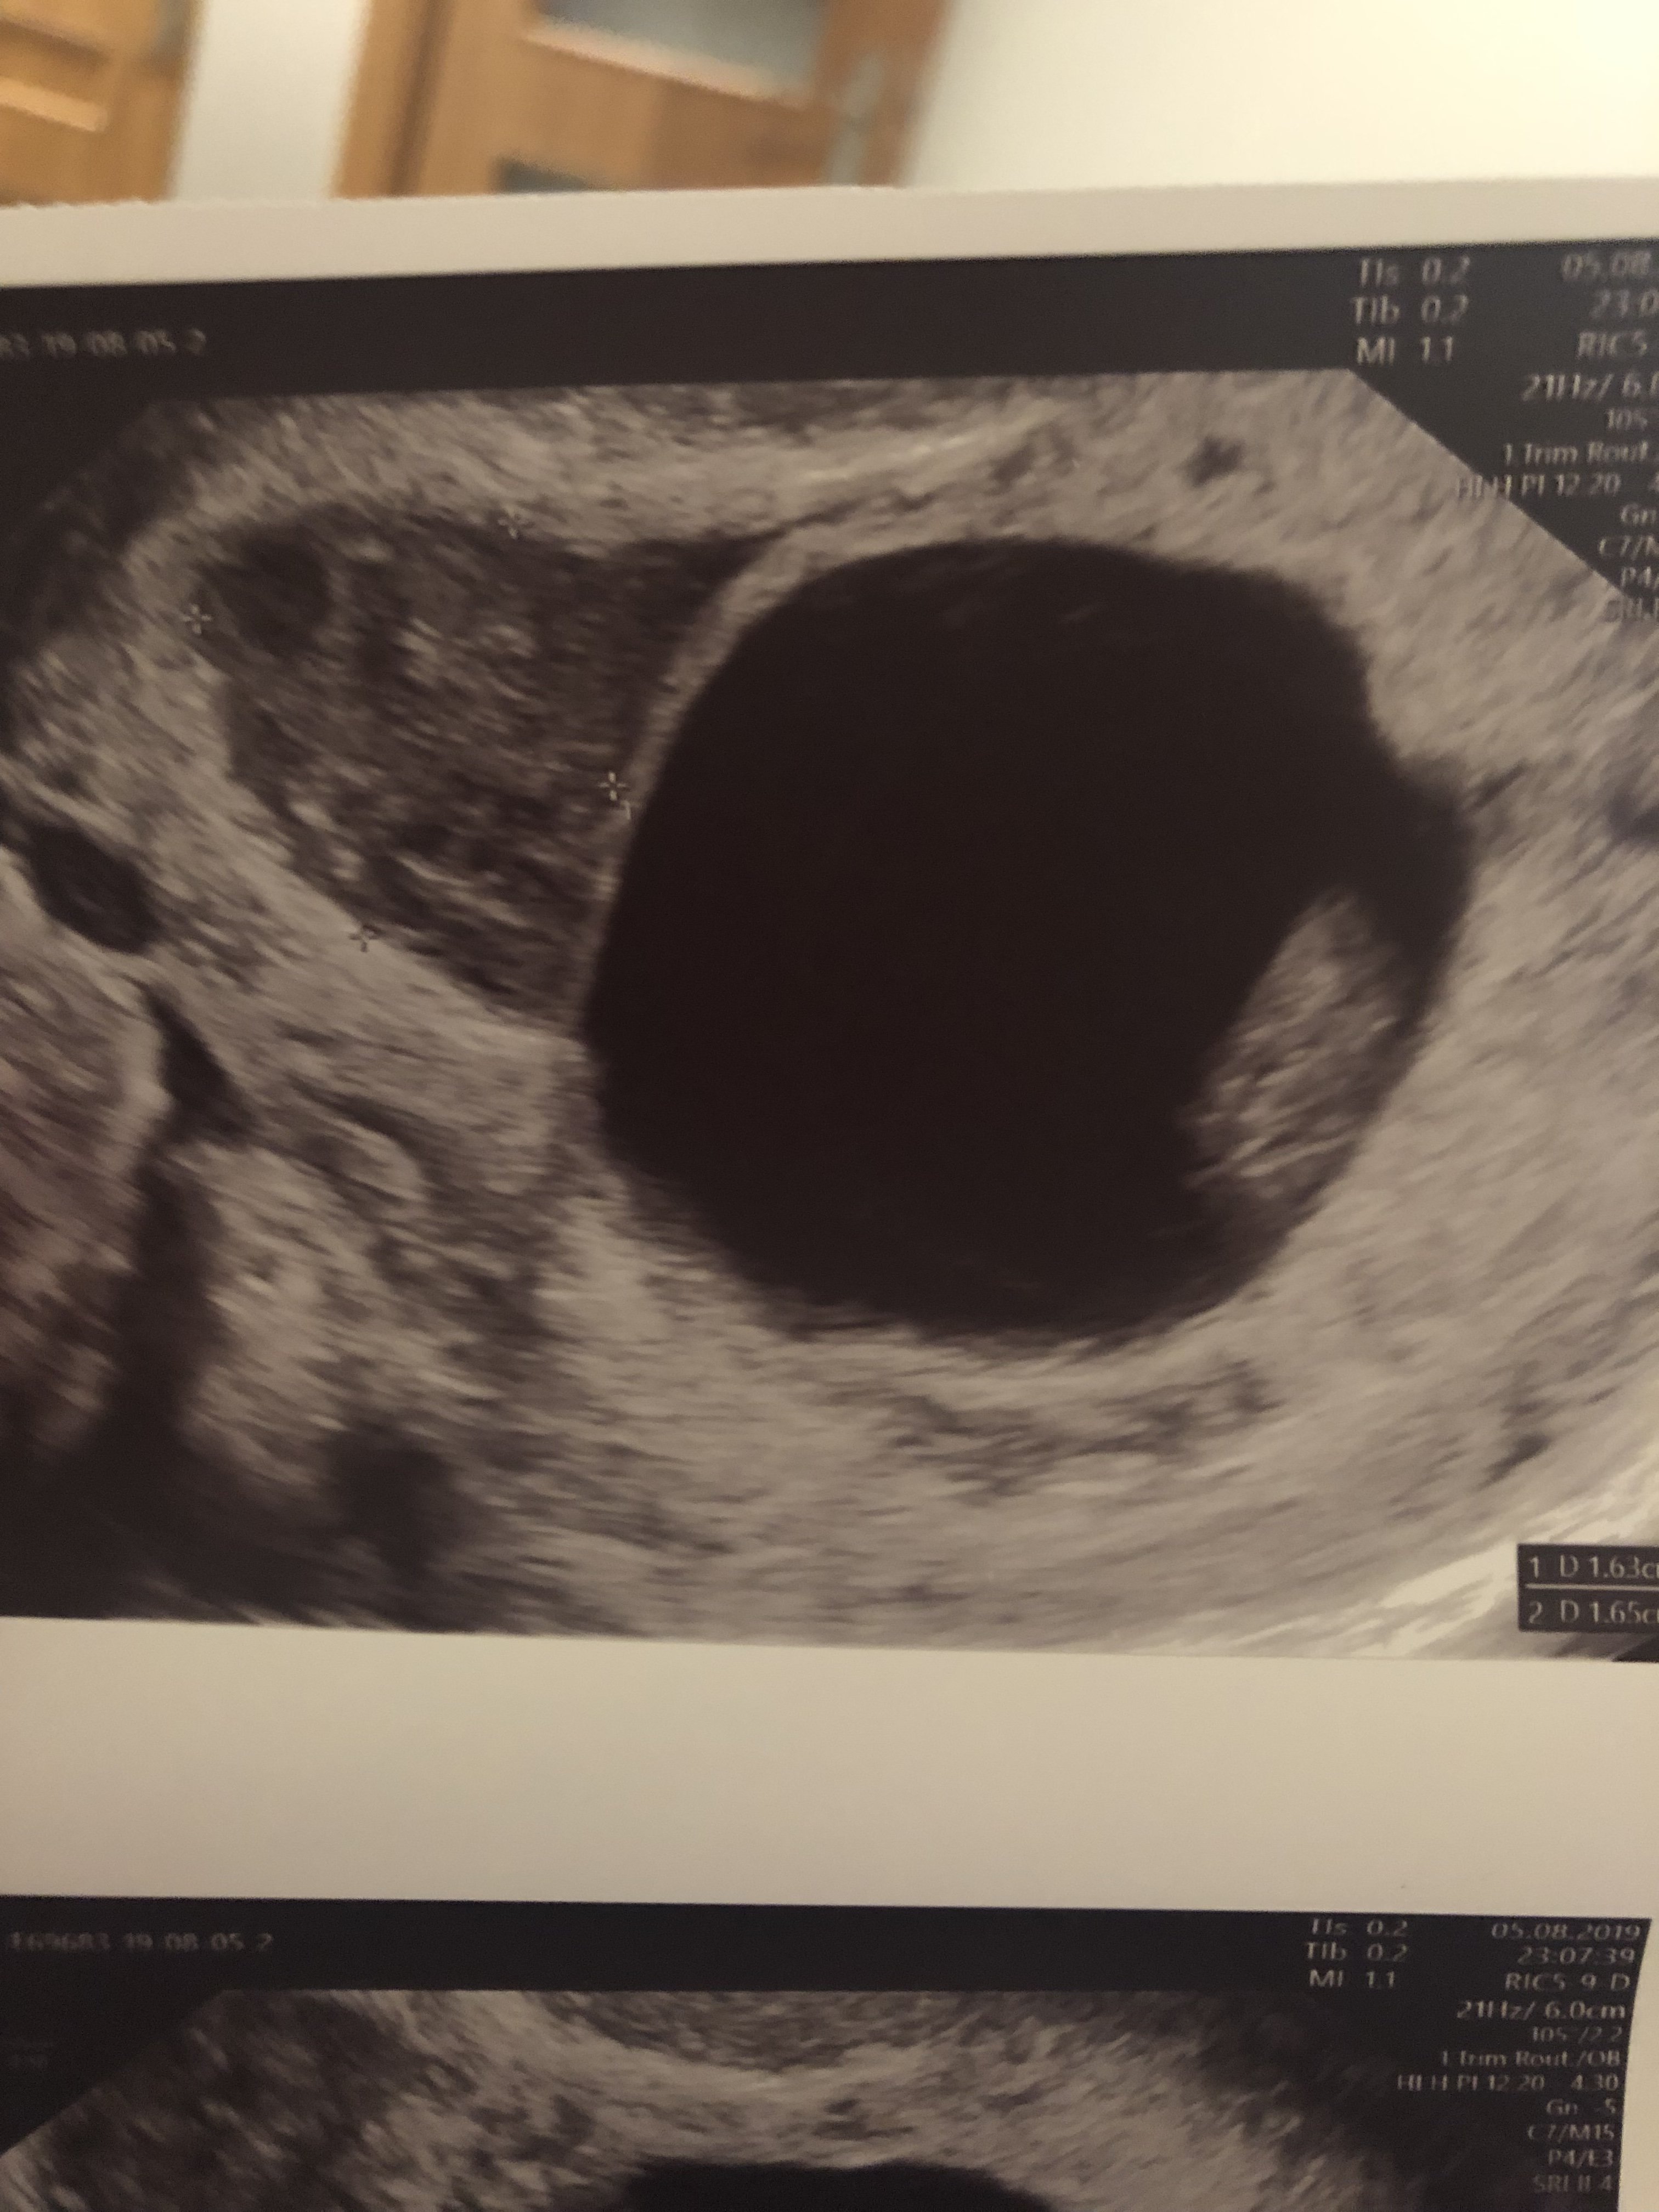

Wróciłam już do domu. Z jednej strony ogromna radość, bo serduszko bije, dzidzia rośnie, a nawet wyprzedza swój wiek wg miesiączki. Ma już 3,1cm i wg usg jest to 10t0d. Super było je zobaczyć chociaż przez pare sekund. Zła wiadomość jest taka, ze krwiak jest dalej... umiejscowienie w miarę „dobre”, ale muszę bezwzględnie cały czas dalej leżeć... no nic trzeba się poświecić, dla dziecka wszystko. Załączam fotki: na jednej dzidzia, a na drugiej z lewej górnej strony widać krwiak.

• CA271B15-AD56-4884-9BD6-C6364CC427A3.jpeg

CA271B15-AD56-4884-9BD6-C6364CC427A3.jpeg

1,1 MB · Wyświetleń: 150